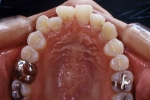

初診時